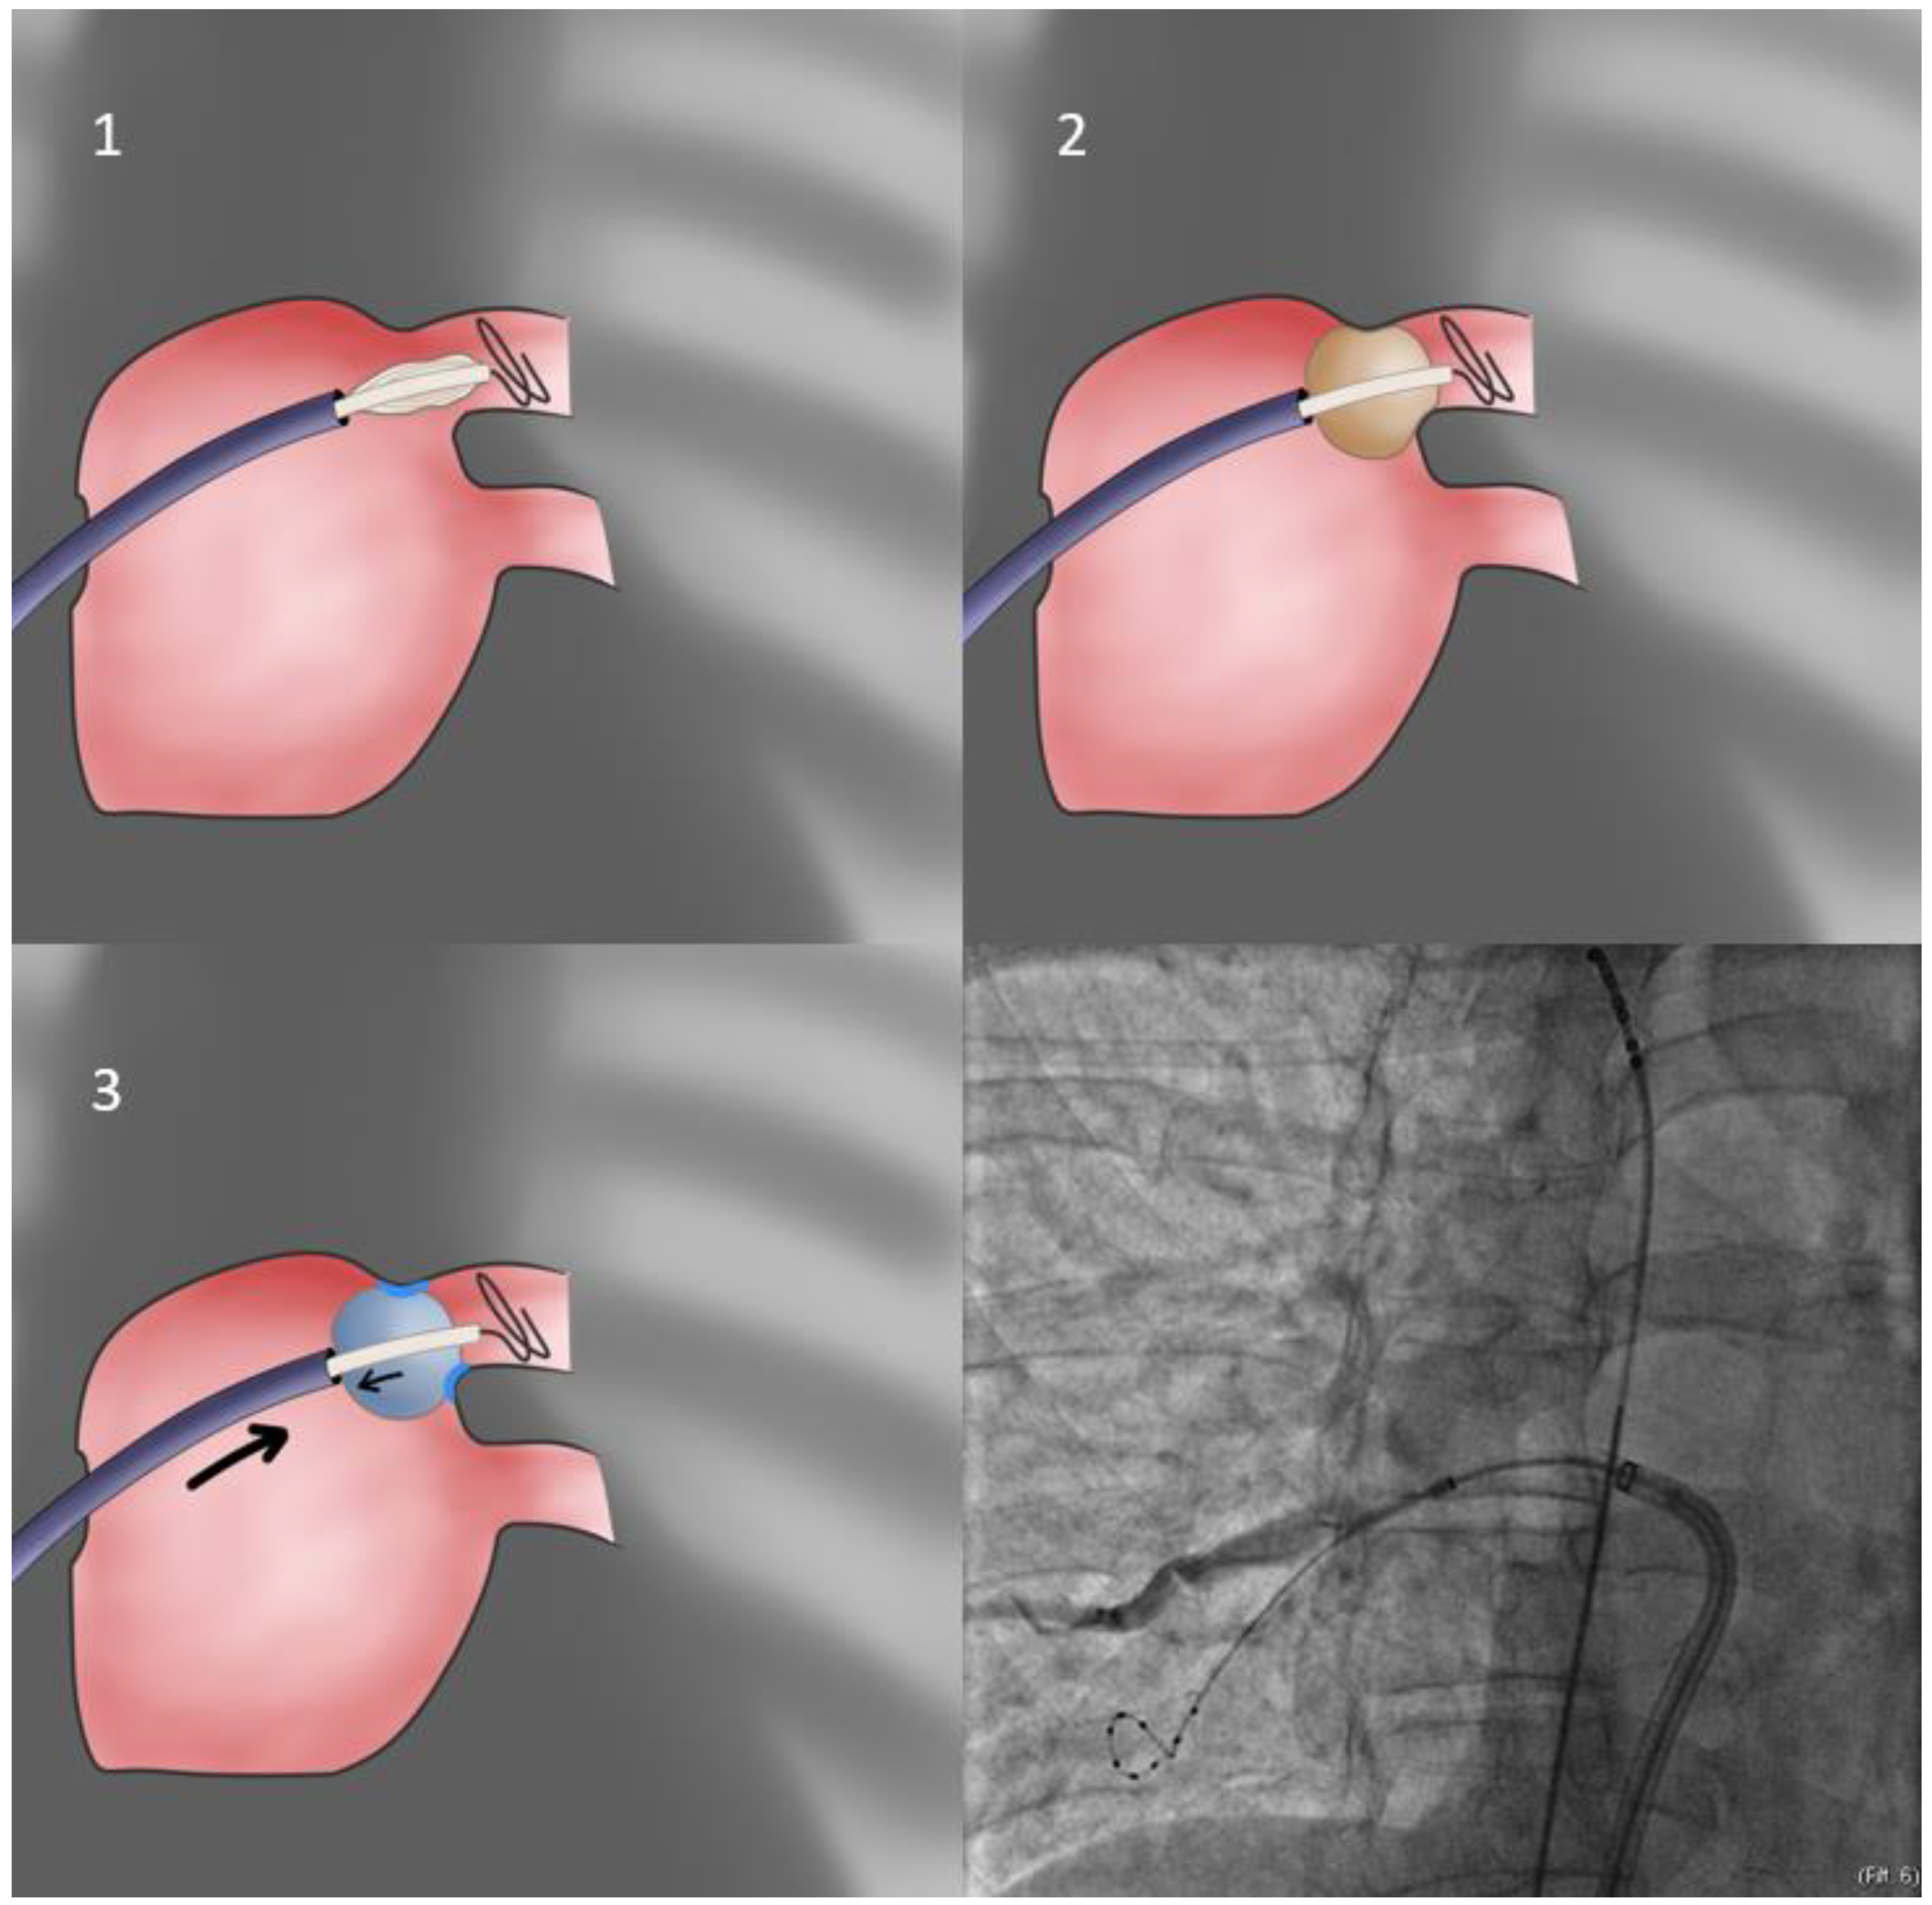

- Our first approach is using the sheath as the support for PV sealing (FlexCath based direct approach—Figure 1). With the whole system (Achieve catheter, cryoballoon and sheath) in contact and the sheath slightly flexed, we aim to align its distal part with the axis of the balloon and the Achieve catheter. Given that a vein may change the orientation of its course very near its antrum, it is the proximal part of the Achieve catheter that should be used for defining proper system alignment [53].